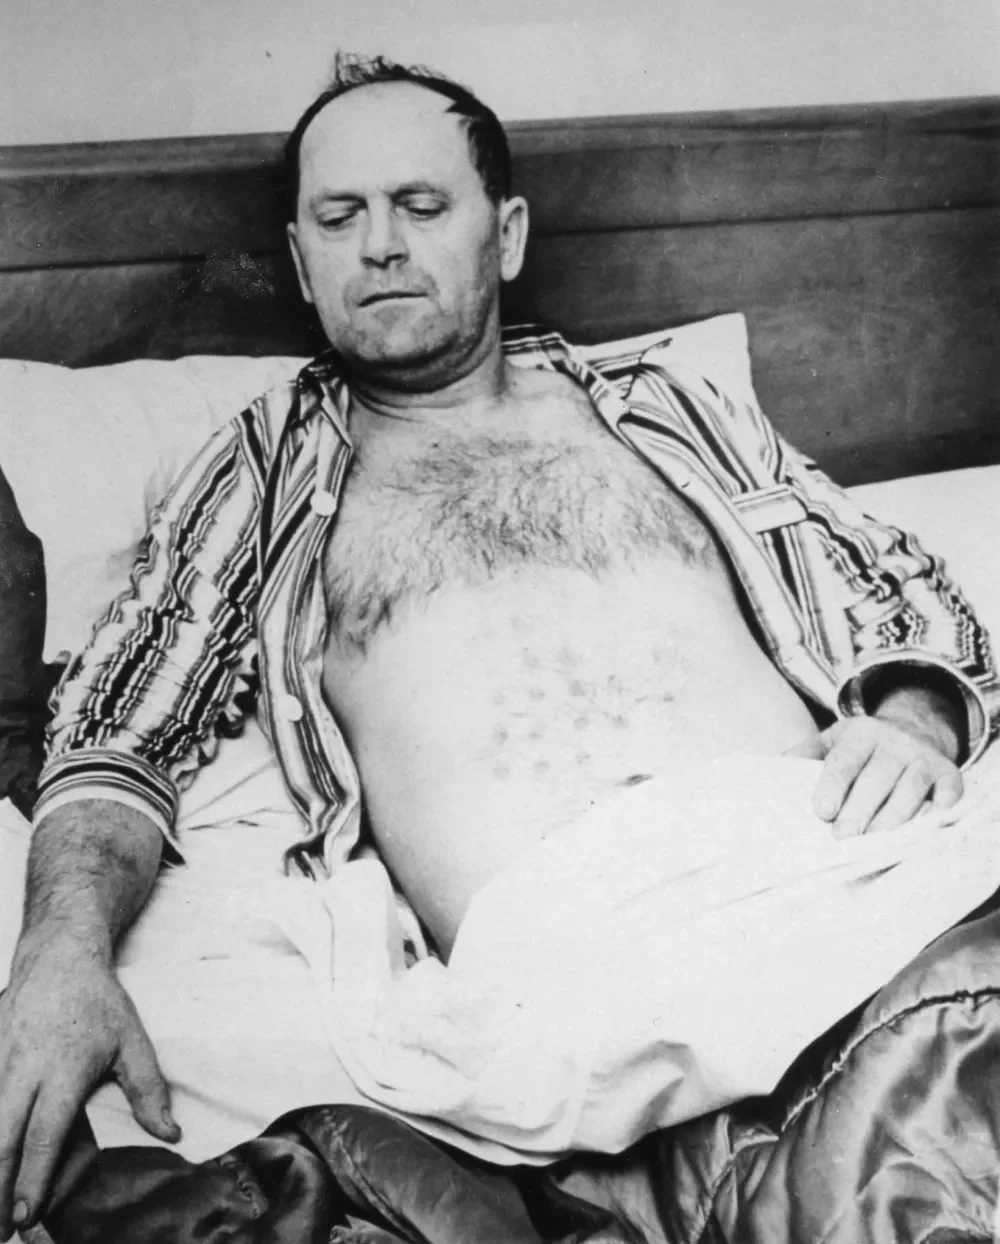

米哈拉克迷失了方向,感到恶心和眩晕。他跌跌撞撞地穿过森林,甚至呕吐了几次。最终,他回到了法尔肯湖汽车旅馆,然后乘坐灰狗巴士返回温尼伯。在那里,他被送往慈悲健康中心急诊室接受治疗。

医生的诊断令人困惑:他的胸部和腹部有烧伤,烧伤愈合后形成了网格状的凸起疤痕。这种图案与他描述的飞行器排气面板的网格孔完全吻合。更令人不安的是,在接下来的几周里,他持续遭受腹泻、头痛、晕厥和体重下降的折磨。他甚至去了明尼苏达州罗切斯特的梅奥诊所进行全面检查。那里的精神科医生得出结论:这是一个"非常务实、脚踏实地、不会编造故事"的人。

消息很快传播开来。《温尼伯论坛报》以"我被UFO烧伤"为标题报道了他的故事。加拿大皇家骑警、皇家加拿大空军、加拿大卫生部和国防部,甚至美国空军(作为康登委员会的一部分)都介入了调查。一个普通的蓝领工人,一夜之间成为了媒体和公众的焦点。

1968年1月,距离最初的烧伤已经过去了八个月,米哈拉克告诉媒体他的烧伤又出现了。记者拍摄了他腹部的照片,显示出一排排均匀分布的痕迹。这些照片至今仍然是这个案件中最令人不安的证据之一。怀疑者指出,这些后期出现的痕迹与他最初的烧伤图案"几乎没有相似之处”,暗示这可能是人为制造的。但支持者反驳说,为什么一个蓝领工人要花费数十年时间精心策划一个骗局?

1999年10月28日,斯特凡·米哈拉克在维多利亚医院去世,享年83岁。他的儿子斯坦说,父亲临终前没有做出任何"坦白”,说这一切都是恶作剧。也没有任何人站出来说他们帮助米哈拉克策划了这个骗局。斯坦回忆道,在他父亲去世前住在医院时,医生在他的腹部皮下仍然可以摸到那些圆形疤痕组织。那个网格图案,似乎永远地刻在了他的身体里。